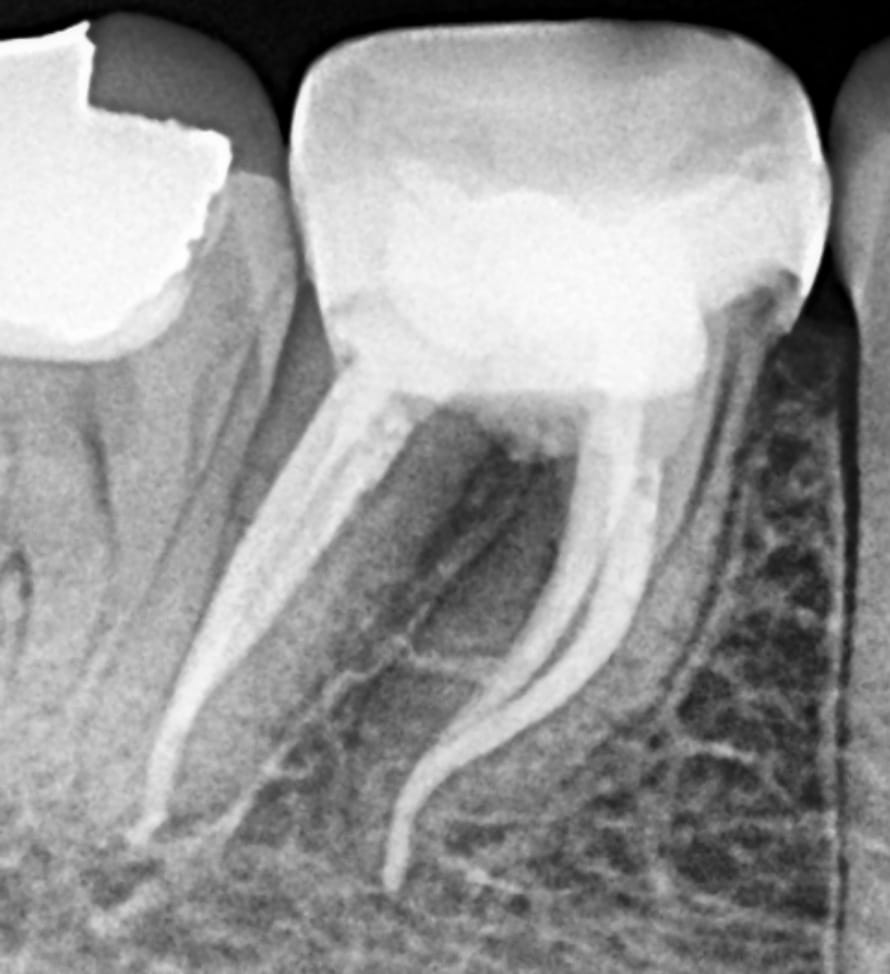

A case of tooth #46 showing radiolucency in the furcation area related to perforation. Patient had this tooth done 5 years ago and started to feel a dull pain recently.

Pre-operative X-ray showing 5 years old perforation and bone obturation

Post-operative x-ray

Mesial shift

Before and after